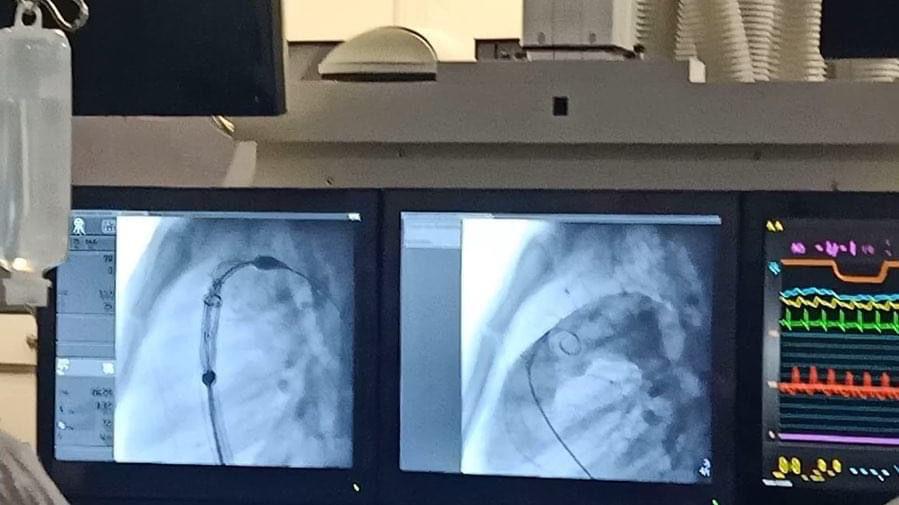

نجحت مستشفيات جامعة عين شمس في إجراء زراعة صمامات رئوية لثلاث حالات عن طريق القسطرة، وقالت الدكتورة عزة الفقي أستاذ ورئيس قسم القلب بكلية الطب جامعة عين شمس، إن هذه التقنية تعد فتحاً علمياً جديداً، لافتة إلى أن هذه التقنية مكلفة للغاية وتحتاج تكاتف جهود العديد من المؤسسات الحكومية ومنظمات المجتمع المدني.

وأضافت الدكتورة مي حمدي السيد أستاذ القلب ومؤسس وحدة عيوب القلب الخلقية بقسم القلب بطب جامعة عين شمس أن تنفيذ هذه التقنية تم بالتعاون مع الدكتور زياد حجازي أستاذ زائر من الولايات المتحدة الأمريكية، لافتة إلى أن تقنية الصمام الأورطي موجودة في مصر منذ سنوات ولكنها لأول مرة تنفذ في الصمامات الرئوية.

وأشارت إلى أن هذه التقنية تم تنفيذها أيضاً في مركز طبي بأسوان وفي جامعة القاهرة، واستعرضت الدكتورة هبة عطية أستاذ أمراض القلب بكلية طب جامعة عين شمس، خطوات التحضير لتنفيذ هذه التقنية والتي استغرقت مراحل عديدة لتحديد الحالات المناسبة، وقالت: «نأمل أن تكون جامعة عين شمس مركزا للتدريب ونقل الخبرات في هذا المجال الجديد».